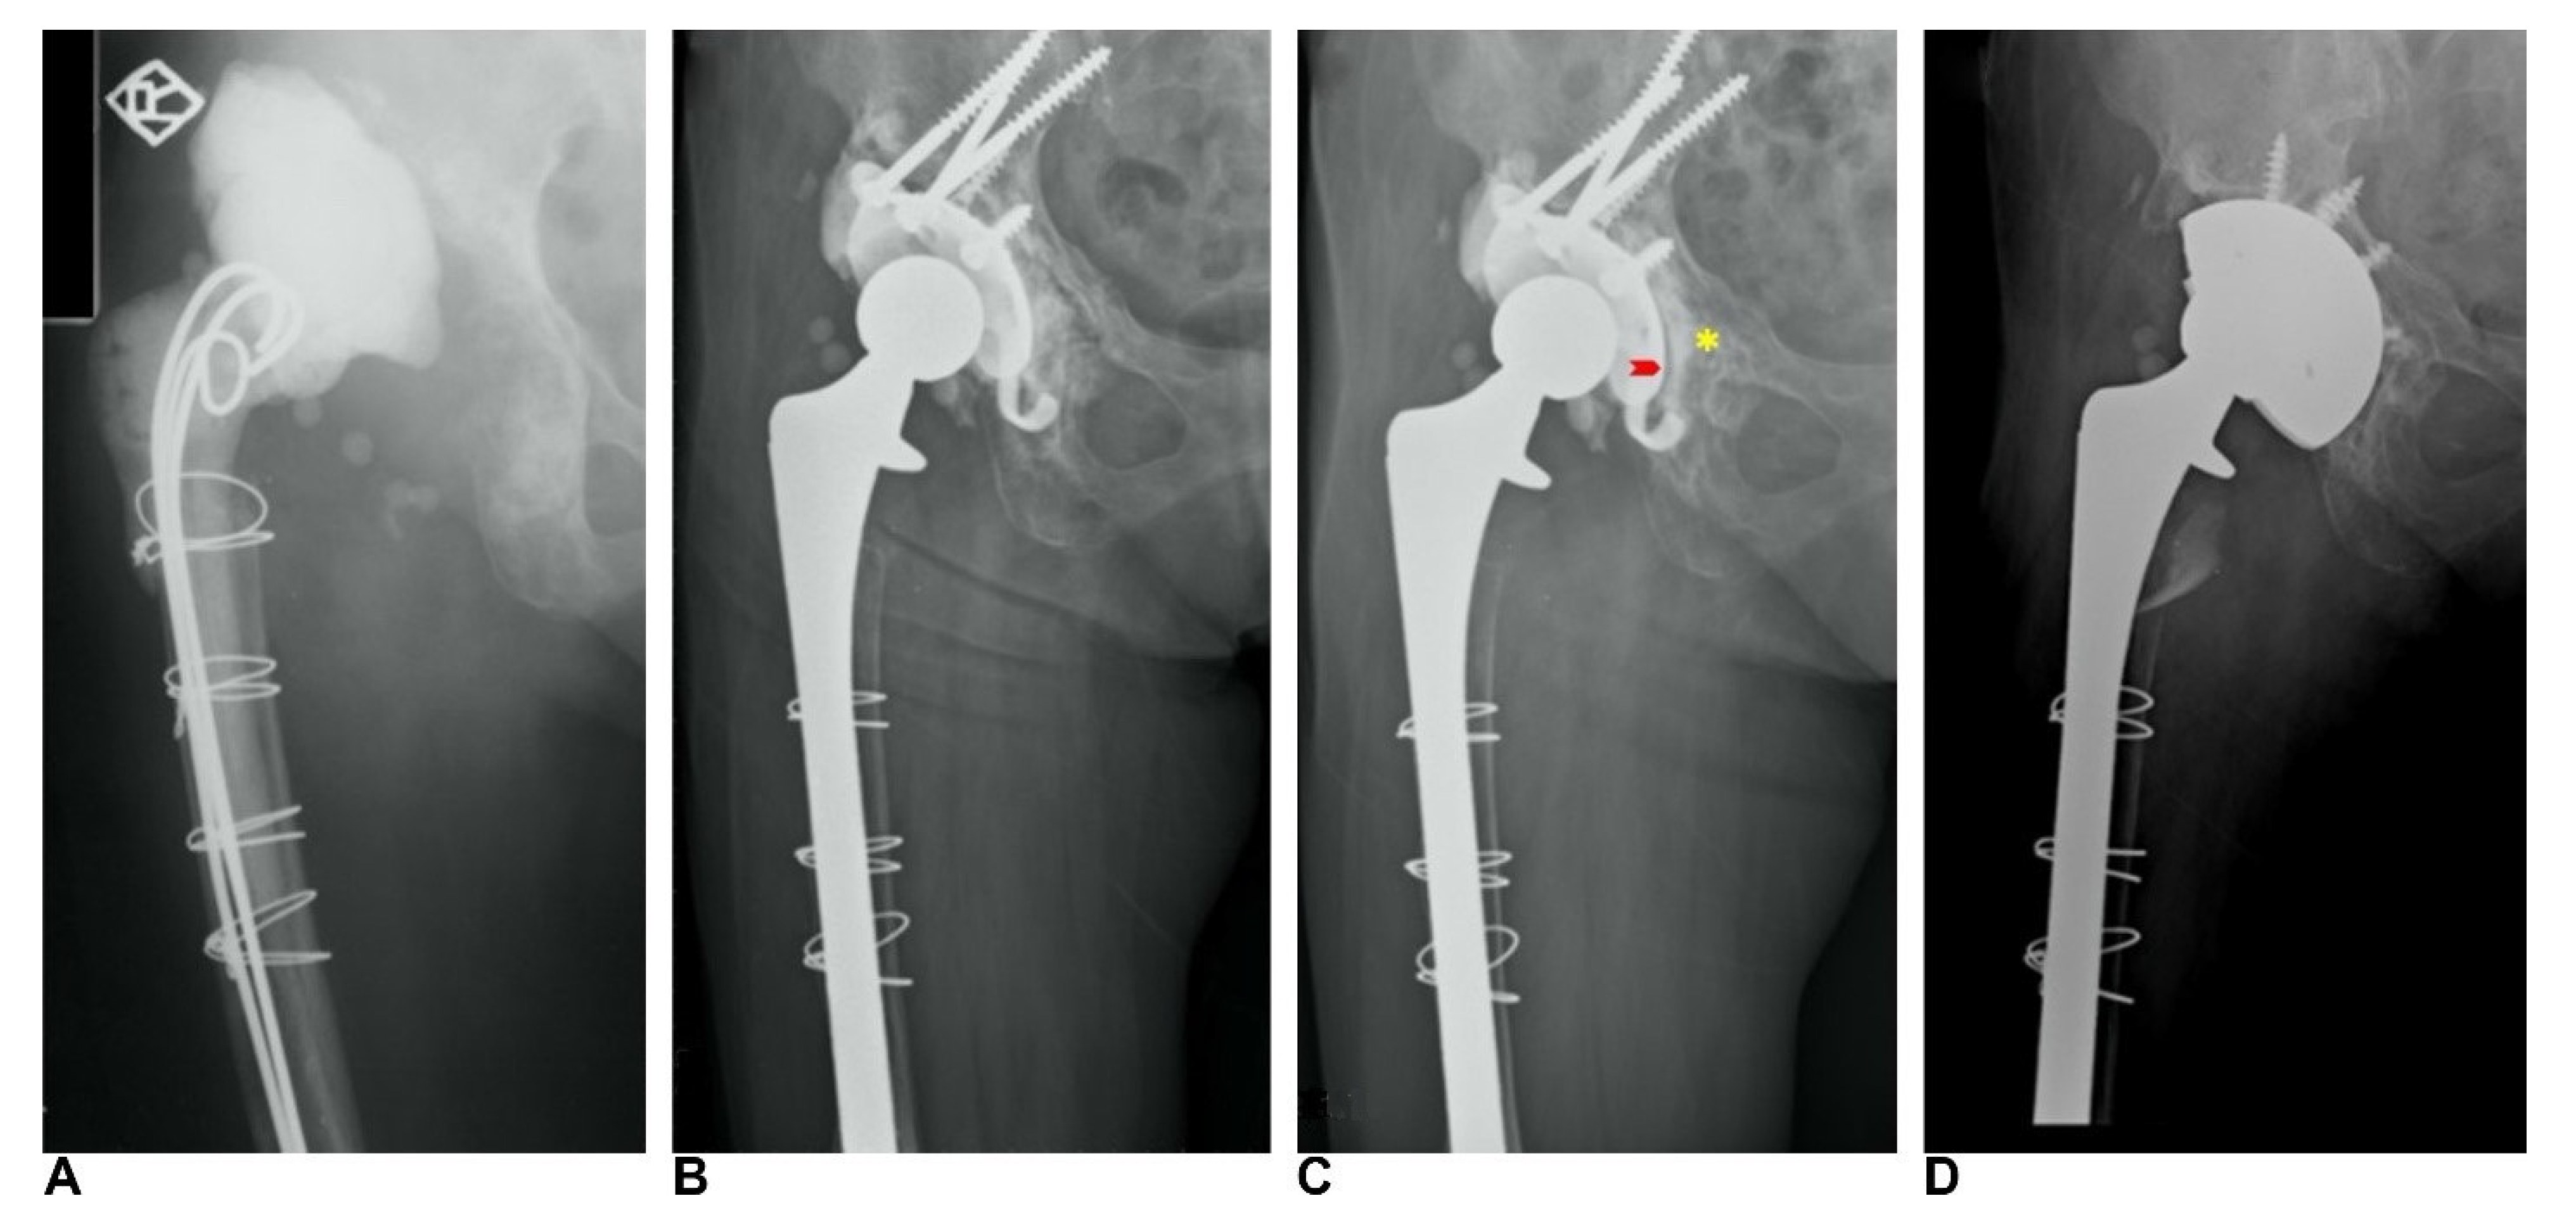

2.2. Surgical Procedure